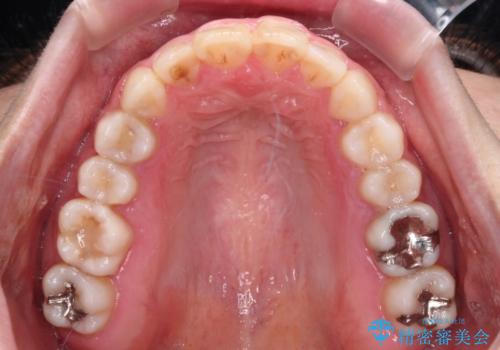

- ワイヤーではない矯正治療があると聞いたとのことで来院された患者様です。

長年前歯のデコボコを気にしていたもののワイヤー矯正に抵抗があり躊躇していたそうですが、インビザラインなら治療してみたいとのことで相談にいらっしゃいました。

インビザライン適用の歯列であったため、歯と歯の間を削るIPRを用いて改善することとしました。

お仕事柄、長時間のマウスピース装着が苦ではなかったので、歯列はすぐに整いましたが、ゆっくりとした交換頻度であったので、2年ほどの治療期間を要しました。